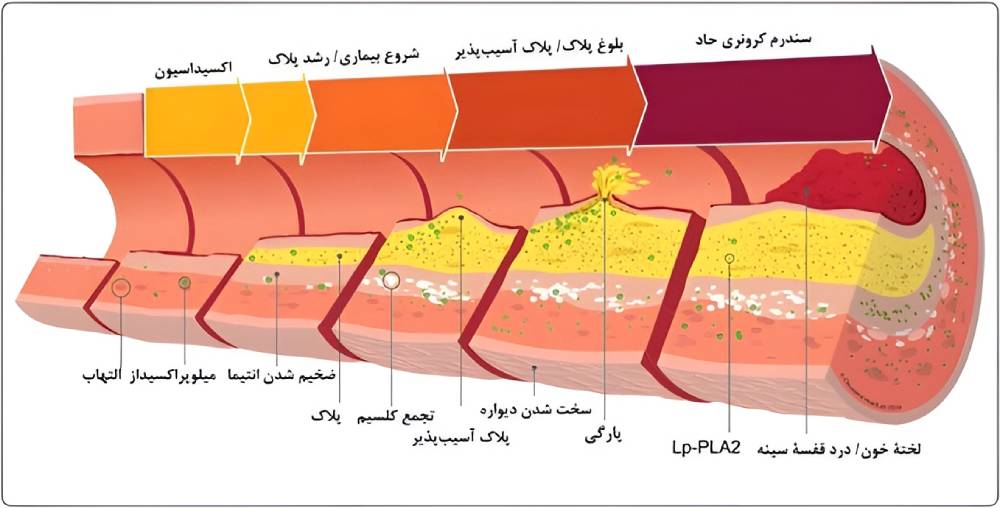

سکته قلبی یا انفارکتوس میوکارد زمانی رخ میدهد که جریان خون به قلب به شدت کاهش پیدا کند یا مسدود شود. این گرفتگی معمولاً پیامد جمع شدن چربی، کلسترول و مواد دیگر در شریانهای کرونری قلب است. به رسوبهای چرب و حاوی کلسترول پلاک گفته میشود. اصطلاح پزشکی برای فرایند تجمع پلاک تصلب شرایین یا آترواسکلروز است.

پلاک گاهی پاره میشود و لختهای را تشکیل میدهد که جریان خون را مسدود میکند. قطع شدن جریان خون به بخشی از عضلۀ قلب آسیب میزند یا آن را تخریب میکند.

دلایل سکته قلبی

اکثریت غالب سکتههای قلبی پیامد انسداد عروق خونی مسئول خونرسانی به قلب است. انسداد رگها غالباً نتیجۀ جمع شدن پلاک، یعنی مادۀ چسبناکی است که داخل شریانها جمع میشود. این اتفاق مشابه وضعیتی است که در اثر ریختن روغن داخل سینک آشپزخانه رخ میدهد و باعث گرفتگی لوله میشود. به تجمع پلاک آترواسکلروز یا تصلبشرایین میگویند.

رسوب پلاک درون شریانهای قلب (کرونری) گاهی متلاشی یا پاره میشود. ممکن است لختۀ خون در محل پارگی رسوب گیر کند. اگر لختۀ خون شریان را مسدود کند، خون به عضلۀ قلب نمیرسد و بیمار سکته میکند.